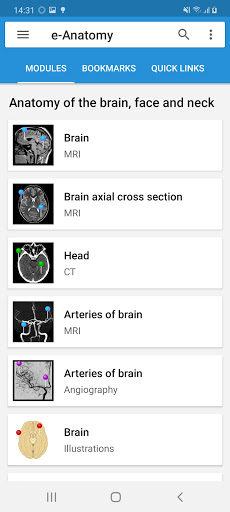

IMAIOS e-Anatomy adalah atlas anatomi manusia untuk dokter, ahli radiologi, mahasiswa kedokteran, dan teknisi radiologi. Dapatkan cuplikan lebih dari 26.000 gambar medis dan anatomi secara gratis sebelum berlangganan atlas anatomi manusia terperinci kami.

e-Anatomy didasarkan pada atlas daring IMAIOS e-Anatomy yang telah memenangkan penghargaan. Bawalah referensi anatomi manusia terlengkap, ke mana pun Anda pergi, di perangkat seluler atau tablet Anda.

e-Anatomy memiliki lebih dari 26.000 gambar yang berisi serangkaian gambar dalam tampilan aksial, koronal, dan sagital serta radiografi, angiografi, gambar diseksi, bagan anatomi, dan ilustrasi. Semua gambar medis diberi label dengan cermat, lebih dari 967.000 label tersedia dalam 12 bahasa termasuk Terminologia Anatomica Latin.

- Dua modul baru: Otak - TOF dan Angiografi Otak, Atlas anatomi neurovaskular normal dari arteri otak pada angiografi serebral. - Antarmuka telah dikerjakan ulang. - Tab baru bernama "QuickLinks" tersedia, mengirimkan modul di bagian tubuh manusia dan memungkinkan Anda melakukan perjalanan cepat ke modul yang Anda cari. Bug kecil -Fixed.